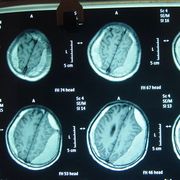

- 数字减影血管造影技术,颅内动脉瘤介入治疗,湘雅护理学院,颅内动脉瘤,颅内动脉瘤系指脑动脉壁的异常膨出部分,是引起自发性蛛网膜下腔出血的最常见原因。病因-尚不甚清楚,但以先天性动脉瘤占大部分。任何年龄可

脑动脉瘤- 5.0共11页

- 颅内动脉瘤介入治疗的护理,主讲人杨鑫,。,一、概述颅内动脉瘤时由于局部血管异常改变产生的脑血管样突起。其主要症状多由出血引起,部分因瘤提压迫,动脉痉挛及栓塞造成。,,,,,,,,,,,,二、颅内动脉瘤介入适应症和禁忌症适应症、几乎所有的动脉